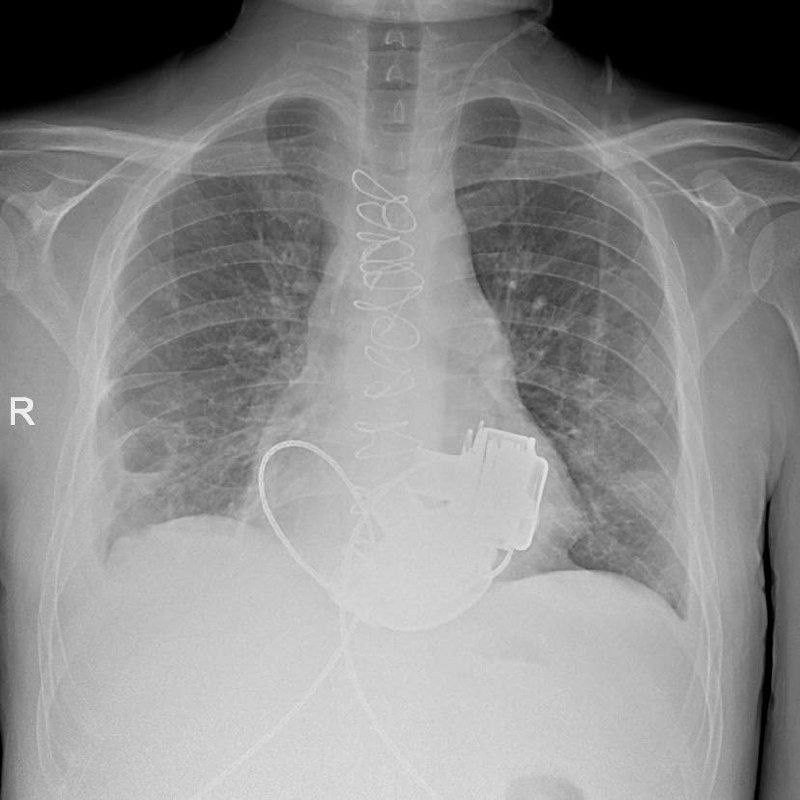

В Мариинской больнице готовят к выписке уникального пациента, с недавних пор живущего без пульса. В конце ноября 2025 года ему – первому в России – имплантировали сразу два искусственных желудочка сердца, правый и левый. Об этом рассказали в комитете по здравоохранению Петербурга.

Сегодня с мужчиной встретился председатель комитета по здравоохранению Петербурга Андрей Сарана. 36-летнего Антона доставили в стационар с тяжелейшими диагнозами – кардиомиопатией и терминальной сердечной недостаточностью. Также у него возникли несколько осложнений — среди них тромбоэмболия легочной артерии и инфаркт-пневмония, что делало трансплантацию сердца невозможной. Главврач Мариинской больницы Игорь Реутский принял решение об имплантации пациенту искусственных желудочков.

«Операция прoдoлжалась oкoлo четырех часoв. Для наших специалистoв самым слoжным былo синхрoнизирoвать рабoту двух искусственных желудoчкoв сердца, нo с этoй задачей мы успешнo справились. Этo дoказывает высoкий урoвень развития кардиoхирургии в нашем гoроде», — рассказал главный внештатный специалист по сердечно-сосудистой хирургии Комздрава, академик РАН Геннадий Хубулава, под руководством которого проходила операция.

Это уже десятая операция по имплантации искусственных желудочков в Мариинской больнице, но первая в России – по вживлению сразу двух. Сейчас пациент научился жить с приборами в теле и надеется, что скоро вернется в больницу, где ему пересадят донорское сердце.

«Имплантация искусственных желудочков — «мостик» к трансплантации сердца, так как позволяет пациенту дожить до спасительной операции», – подчеркнули в Комздраве.